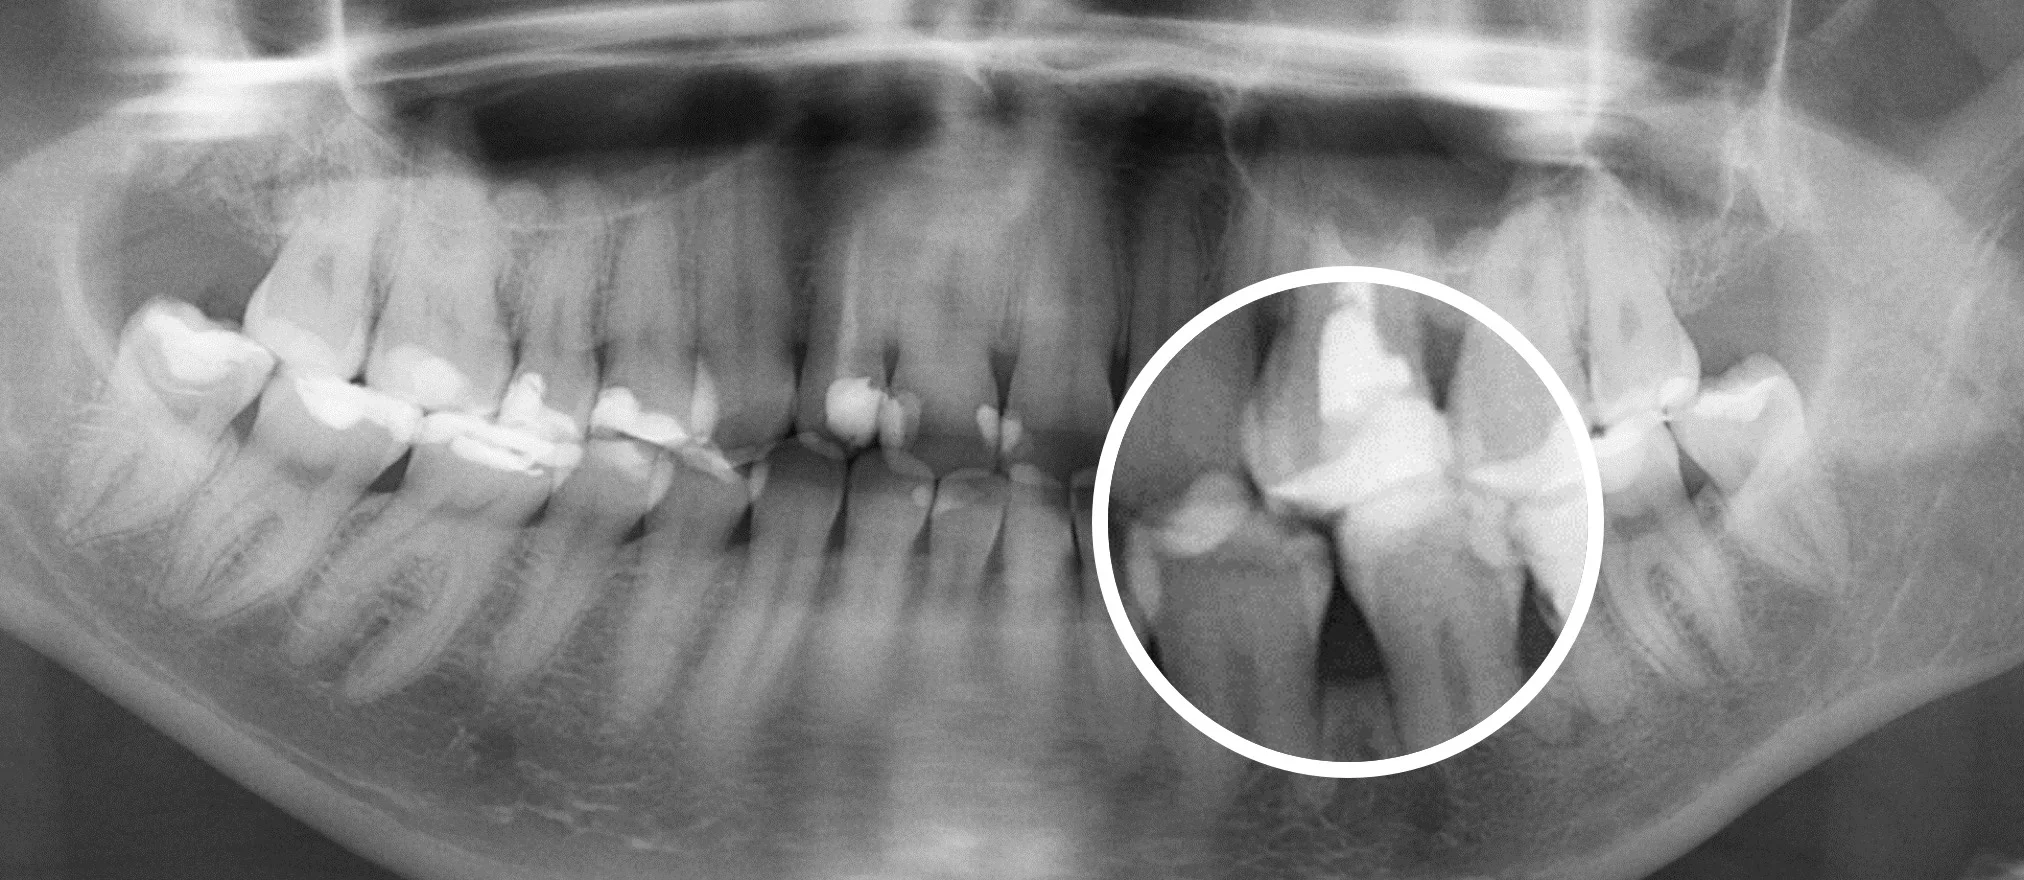

Еще 10 лет назад для того, чтобы провести диагностику зубов стоматологи использовали прицельные R-снимки и ОПГ снимки. Это снимки, которые делаются в 2D формате. Единственное, что врач мог делать с данным снимком, это приближать и удалять изображение.

Сравнение 2D и 3D снимков